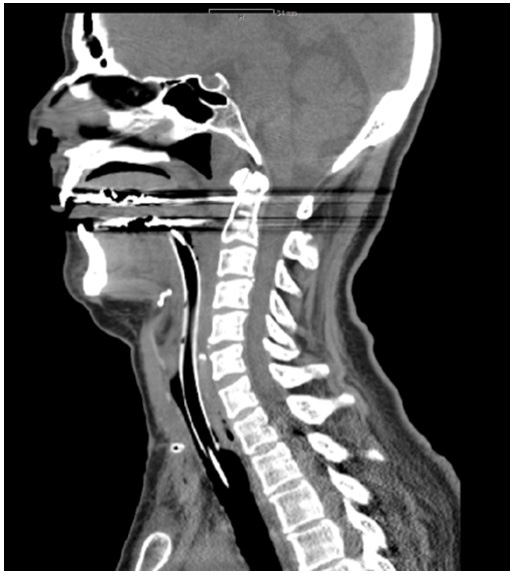

Figure 1: Postoperative CT-scan: Larynx, hypopharynx and parts of the oropharynx heavily edematous.

figure 1